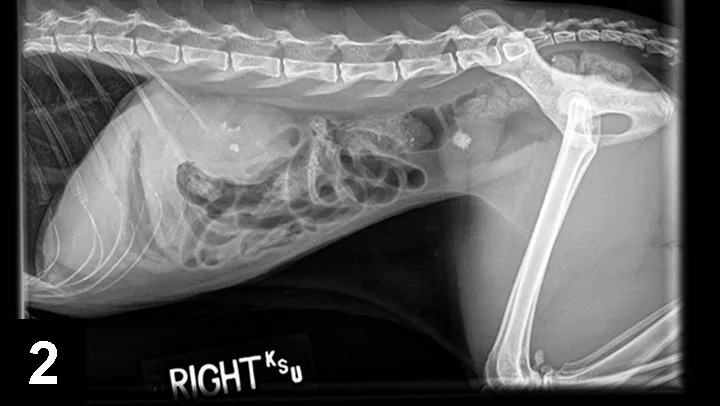

Figure 2. Lateral radiograph of a 9-year-old, castrated domestic long-haired cat with suspected CaOx nephroliths and a single CaOx urocystolith).

Older dogs and cats (8–12 years) are most commonly affected by CaOx uroliths, and concurrent urinary tract infection appears to be rare. CaOx uroliths are typically the most radioopaque of all uroliths and usually easily observed on plain film radiographs (Figures 1 and 2).